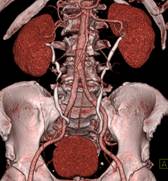

脑血管畸形CTA ,大血管成像:动态容积成像实现大范围动态血管检查

泌尿系成像 肺动脉栓塞 肺透明成像